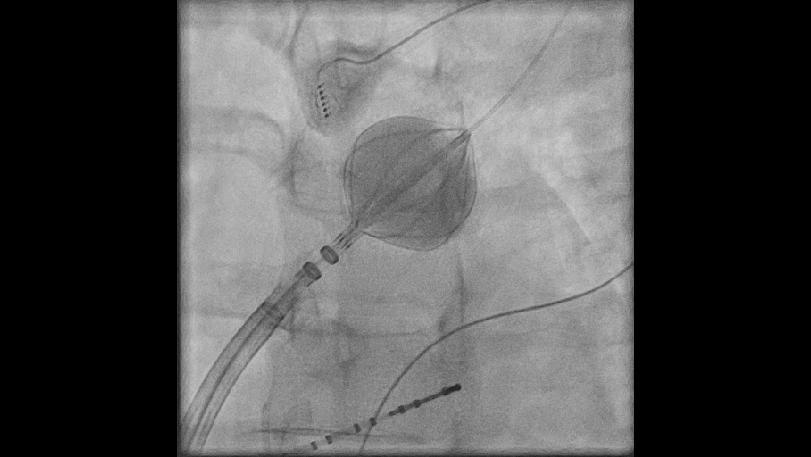

In einigen Behandlungszentren wird vor der Ablationsbehandlung eine Schichtaufnahme vom Herzen (Computertomographie oder Magnetresonanztomographie) durchgeführt. In unserem Hause wird regelhaft unmittelbar vor der Katheterablation eine Rotations-angiographische Bildgebung im Herzkatheterlabor vorgenommen.

Diese dreidimensionale Rekonstruktion ermöglicht eine exakte anatomische Aufarbeitung des linken Vorhofs. Eine detaillierte räumliche Darstellung der Lungenvenen in ihrer exakten Lagebeziehung zum linken Vorhof ist eine wesentliche Voraussetzung für eine erfolgreiche Katheterablation bei Vorhofflimmern.

Anschließend werden von der rechten Leiste aus mehrere millimeterdünne Kunststoffschläuche (Elektrodenkatheter) zum Herzen vorgeschoben und nach Punktion der Vorhofscheidewand (transseptale Punktion) in den linken Vorhof platziert. Mit diesen Kathetern kann der Kardiologe die elektrischen Ströme, die durch das Herz fließen, aufzeichnen und beurteilen. Die eigentliche Behandlung erfolgt dann mit dem Ablationskatheter, dessen Spitzenelektrode mittels Hochfrequenzstrom auf eine Temperatur von 60-70 Grad Celsius erwärmt wird. Dies ermöglicht eine Punkt für Punkt-Verödung von Herzmuskelzellen, sodass eine Isolationslinie entsteht, die die Ausbreitung von störenden elektrischen Impulsen unterbricht und dadurch das Vorhofflimmern verhindert. Mit Hilfe modernster Technologien, die ohne röntgenologische Kontrolle eine exakte dreidimensionale Positionsbestimmung der Elektrodenkatheter ermöglichen, können die einzelnen Verödungsimpulse exakt gesetzt werden.